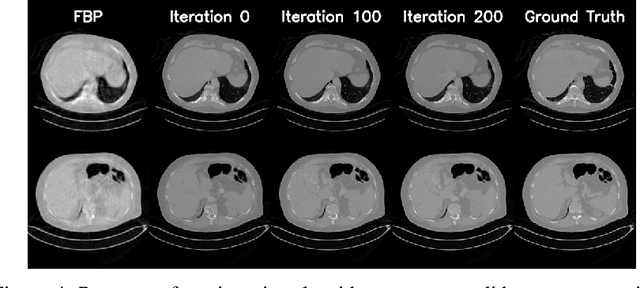

Abstract:We propose an end-to-end differentiable architecture for tomography reconstruction that directly maps a noisy sinogram into a denoised reconstruction. Compared to existing approaches our end-to-end architecture produces more accurate reconstructions while using less parameters and time. We also propose a generative model that, given a noisy sinogram, can sample realistic reconstructions. This generative model can be used as prior inside an iterative process that, by taking into consideration the physical model, can reduce artifacts and errors in the reconstructions.